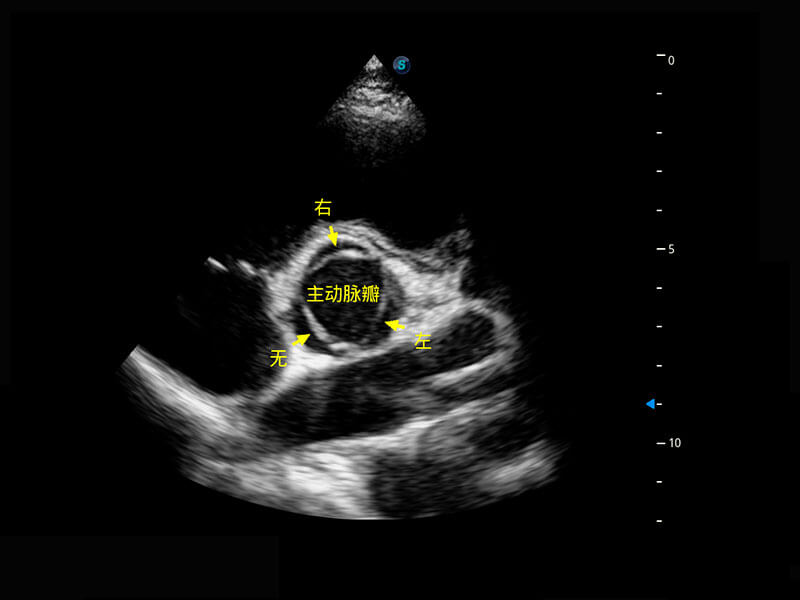

四腔切面

右室双出口

胎心容积成像